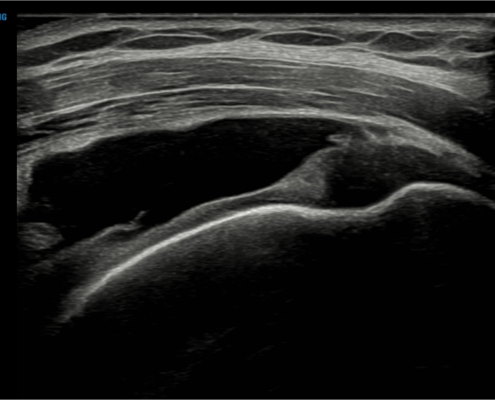

Met echografie kunnen we de schouderpezen goed beoordelen. Met behulp van een echo bepalen we de grootte en locatie van de scheur.

Echografie cuff ruptuur

We kijken naar verschillende soorten scheurtjes:

Gedeeltelijke scheur schouderpees (partiele cuff ruptuur)

Een gedeeltelijke scheur noemen we ook wel een partiele ruptuur. De pees is aan de bovenzijde of aan de onderzijde ingescheurd. Dit kan meerdere pezen tegelijk betreffen.

Volledige scheur schouderpees (full thickness cuff ruptuur)

Bij een volledige cuff ruptuur is de pees helemaal doorgescheurd. De pees trekt zich terug en moet beoordeeld worden door de orthopeed voor een herstellende operatie.